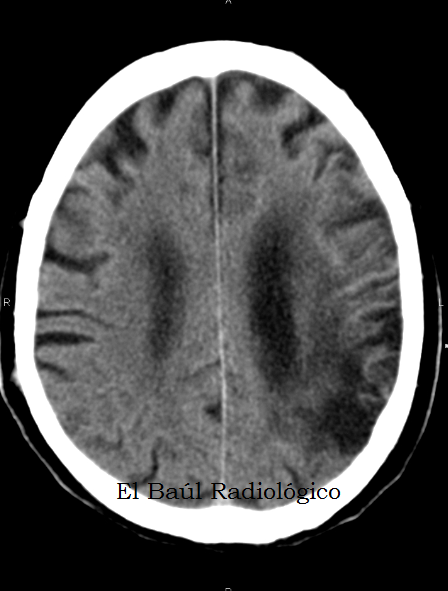

Il termine malacia (molle) identifica l'aspetto che le cellule cerebrali assumono dopo il decadimento, risultando positive alla valutazione ultrasonica (ecogenicità). All'encefalomalacia si associano spesso delle aree "vuote" più o meno diffuse, in corrispondenza delle cellule cerebrali decadute. Si configura quindi una encefalomalacia multicistica (o policistica).